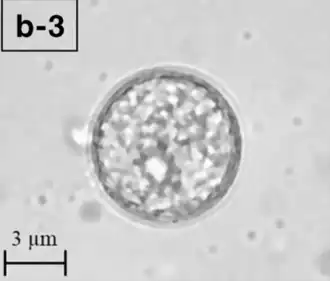

Balamuthia mandrillaris est une amibe hétérotrophe libre, constituée d'un complément standard d'organites entouré d'une paroi cellulaire à trois couches (que l'on pense être constituée de cellulose ou d'un polysaccharide similaire[3]), et avec un noyau cellulaire anormalement grand. En moyenne, un trophozoïte de Balamuthia mesure environ 30 à 120 µm de diamètre. Les kystes se situent également dans cette gamme de dimension[4].